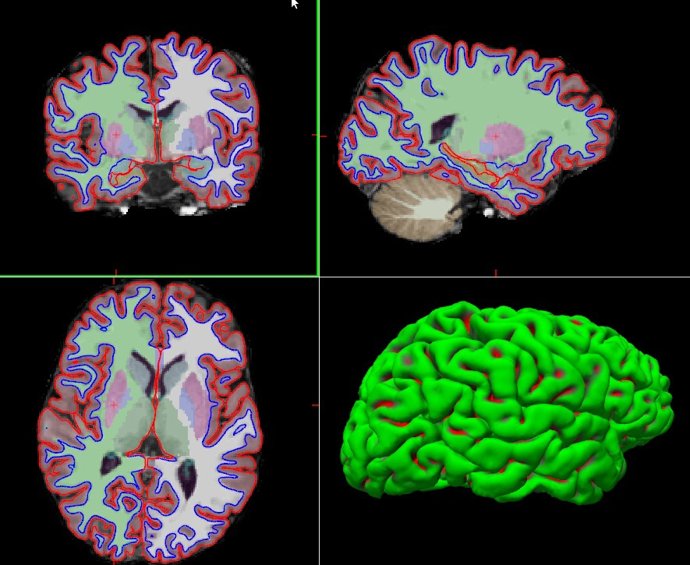

Segmentación de estructuras subcorticales

Un equipo de investigadores, entre los que ha participado el grupo de Psiquiatría de la Universidad de Cantabria, ha descubierto la existencia de cinco variantes genéticas que influyen significativamente en el volumen de estructuras cerebrales subcorticales (putamen y núcleo caudado).

El objetivo del estudio, publicado en la revista 'Nature', ha sido descubrir si hay variaciones comunes (SNPs) en el genoma humano que modifican el volumen de partes del cerebro que son muy importantes para la memoria, la motivación, el comportamiento y que están relacionadas con enfermedades mentales. Para ello, se estudiaron los casos de más de 30.000 personas, combinándose datos de resonancia magnética cerebral y de análisis genéticos (GWAS).